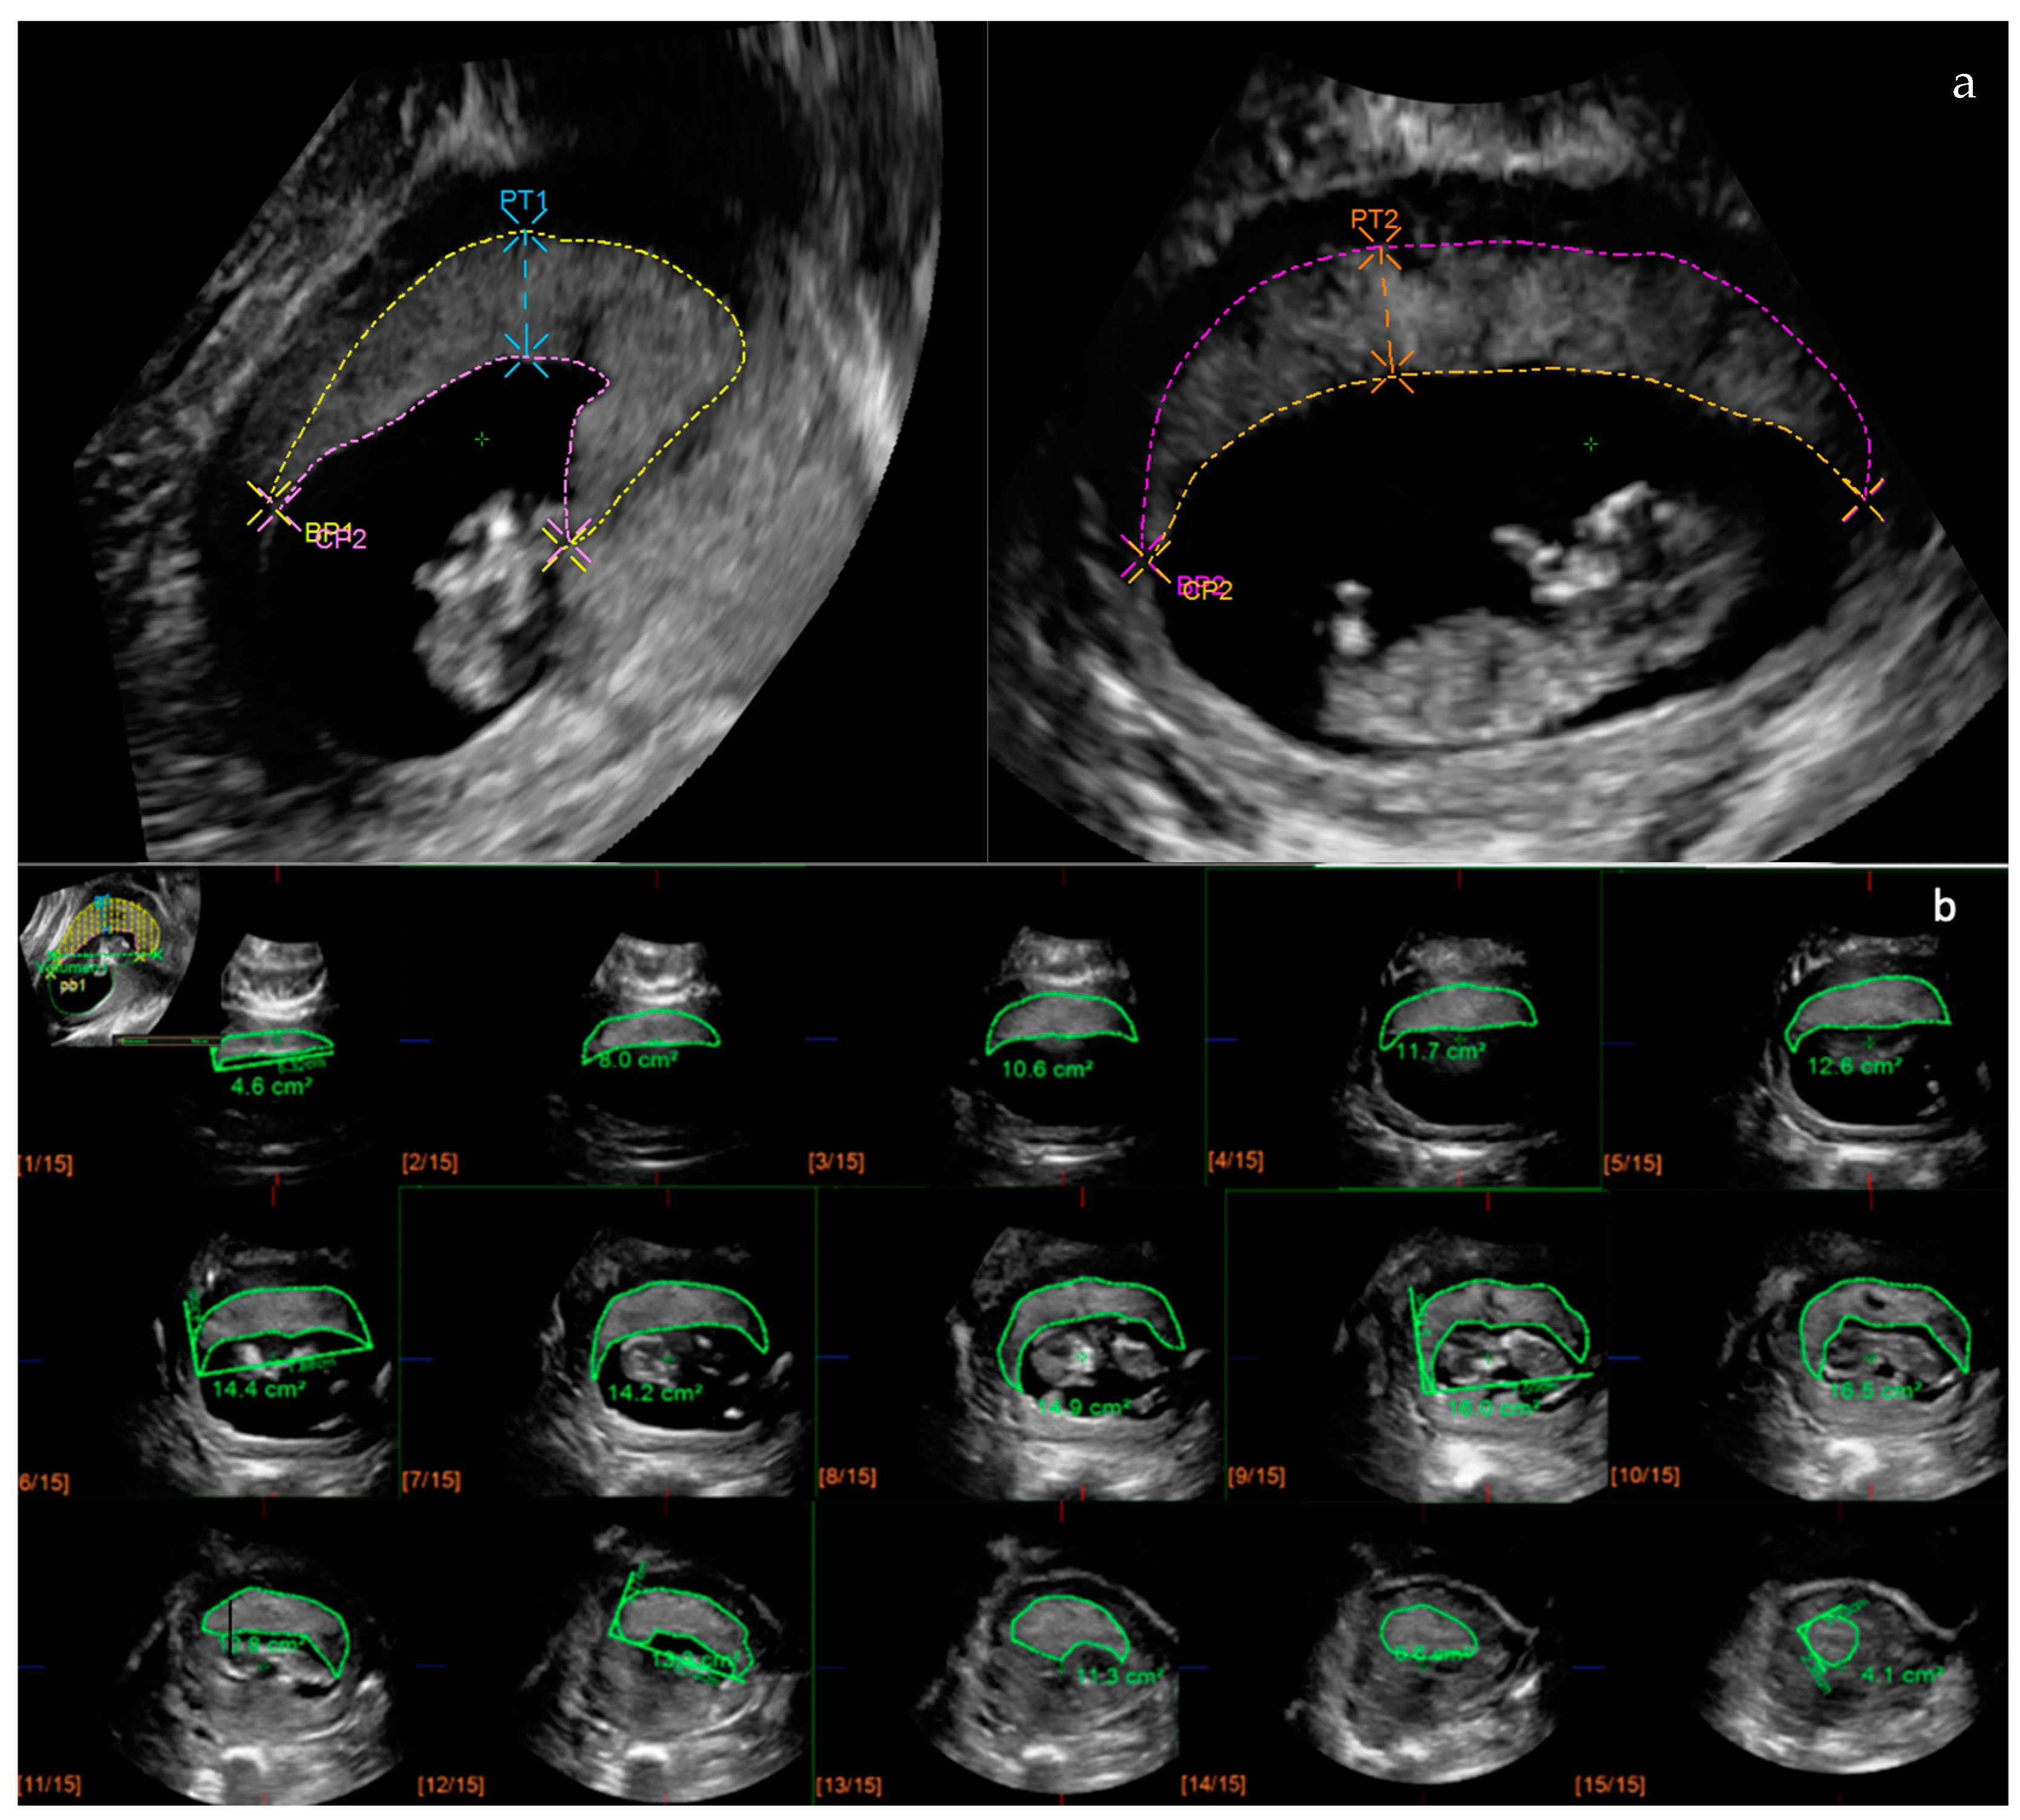

2.2. Placental Ultrasonography